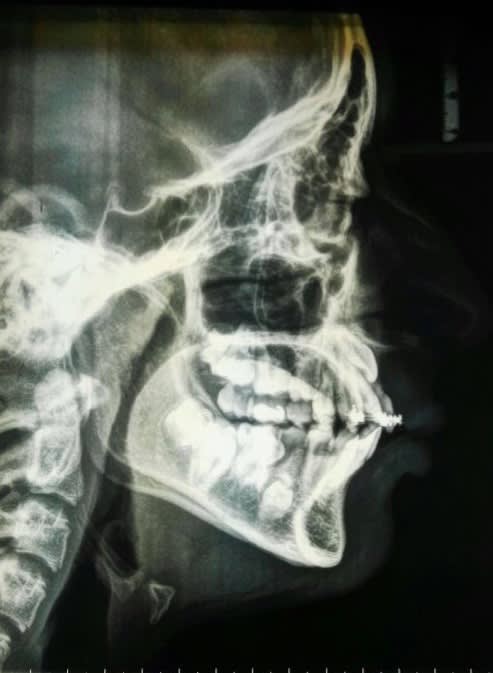

Un confrère m'a envoyé ces photos ( panoramique et téléradiographie) pour avis.

Une reprise d'un traitement orthodontique !

Mon avis:

- Cône Beam

- si les racines des dents incluses n'ont pas terminées leurs évolution, il faudra les extraire et prévoir des implants après correction orthodontique des deux arcades.

Si au contraire les racines sont bien évoluées alors il faudra les faire intégrer dans le plan de traitement orthodontique.

Sinon cela mise à part et avant de critiquer celui qui à commencer le traitement je remarque :

- bracket seulement en anterieur au maxillaire sup

- grosse béance postérieur à droite due à la fois au secteur 1 et 4 . Je n'aime pas du tout les asymmetrie

- 45 ankylosé ( là pas de gros doute )

Conclusion :

Défaut d'éruption asymétrique, , je chercherais du coté d'un syndrome. Perso c'est le genre de cas ou je consulterais le département orthodontique d'une fac.

Cas pluridiscplinaire qui vas demander au niveau de l'ortho une mécanique non classique dans tout les cas, avec probablement de la chir associé.